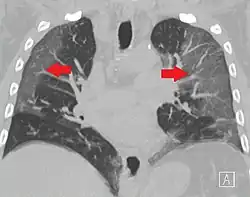

Dégâts pulmonaires

Les études en microscopie électronique et sur coupes histologiques de tissus pulmonaires (faites après autopsies) ont montré que les virions sont dans le poumon essentiellement localisés dans les pneumocytes[204].

Comme dans le cas du SARS, puis du MERS, la Covid se traduit dans l'arbre respiratoire par des lésions alvéolaires diffuses, caractérisées par des phases exsudatives et prolifératives de ces lésions, avec une congestion des vaisseaux capillaires et une nécrose systématique des pneumocytes, et très souvent une atteinte des membranes hyalines, un œdème interstitiel et intra-alvéolaire.

Les autopsies ont aussi révélé de fréquents événements thromboemboliques (« parfois cliniquement insoupçonnés au décès »)[205]. Outre une hyperplasie pneumocytaire de type 2, on a souvent observé une métaplasie squameuse avec atypie et micro-thrombus plaquettaire-fibrine[204],[206],[207],[208],[209].

L'infiltrat inflammatoire est toujours majoritairement composé de macrophages, souvent présents dans la lumière alvéolaire, souvent accompagnés de lymphocytes dans l'interstitium[204]. Des membranes hyalines se forment fréquemment, et une hyperplasie atypique des pneumocytes est également fréquemment constatée post-mortem. Le thrombus plaquettaire-fibrine des petits vaisseaux artériels peut être relié à une coagulopathie apparemment fréquente chez les malades de Covid-19 et qui selon Carsana & al (2020) devrait être l'une des principales cibles du traitement[204].